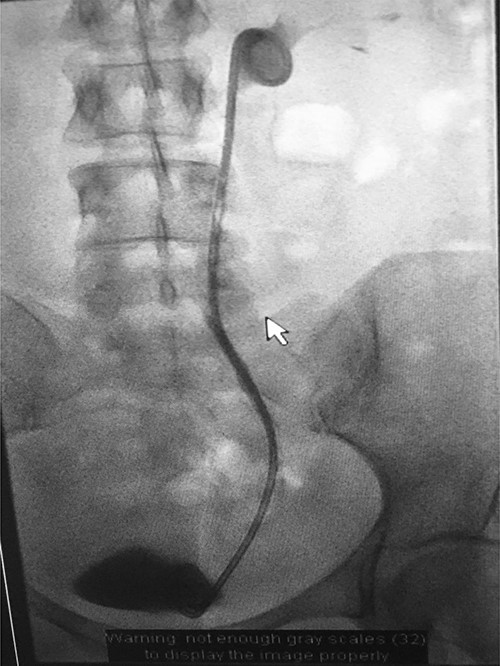

Fluoroscopic images showing the retrograde wire successfully retrieved and brought externally via the nephrostomy site, achieving through-and-through wire access.

A catheter-guidewire exchange was performed to upsize the guidewire to a 0.035-inch stiff guidewire. An 8-Fr, 26-cm nephroureteric stent was inserted over the guidewire in an antegrade manner (Fig. 8). The stent was left to free external drainage. The patient was transferred back to the ward and discharged home the following day. Trial without bladder catheter was successfully undertaken 1 week post-procedure.

Fluoroscopic images demonstrating the successfully re-connected right ureter with a nephroureteric stent in situ.